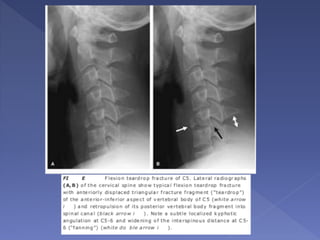

 represents the most severe injury of the cervical spine

 highly unstable injury

 typically involving the lower cervical spine (especially C5)

 there is also complete disruption of all soft tissues at the

level of injury, including the posterior longitudinal ligament,

intervertebral disc, and anterior longitudinal ligament

 typical large triangular fracture fragment of the anteroinferior

margin of the upper vertebral body (teardrop fragment)

 The flexion teardrop fracture can be distinguished from the

similarly named hyperextension teardrop fracture by the

larger size of the triangular fragment and by distraction of

the posterior elements (indicating the flexion mechanism).